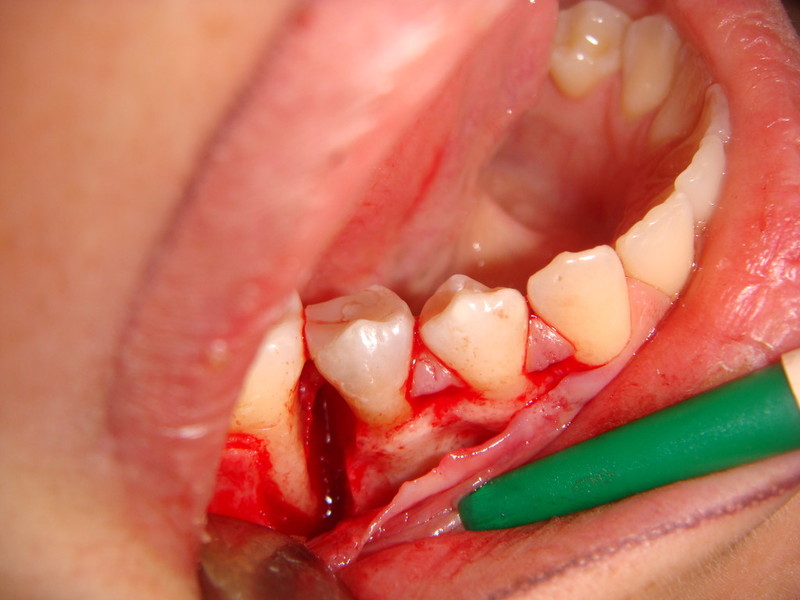

Rigenerazione difetto parodontale di un canino inferiore con materiale eterologo

rigenerazione grave difetto parodontale a carico del 46

rigenerazione grave difetto parodontale a carico una intera emiarcata